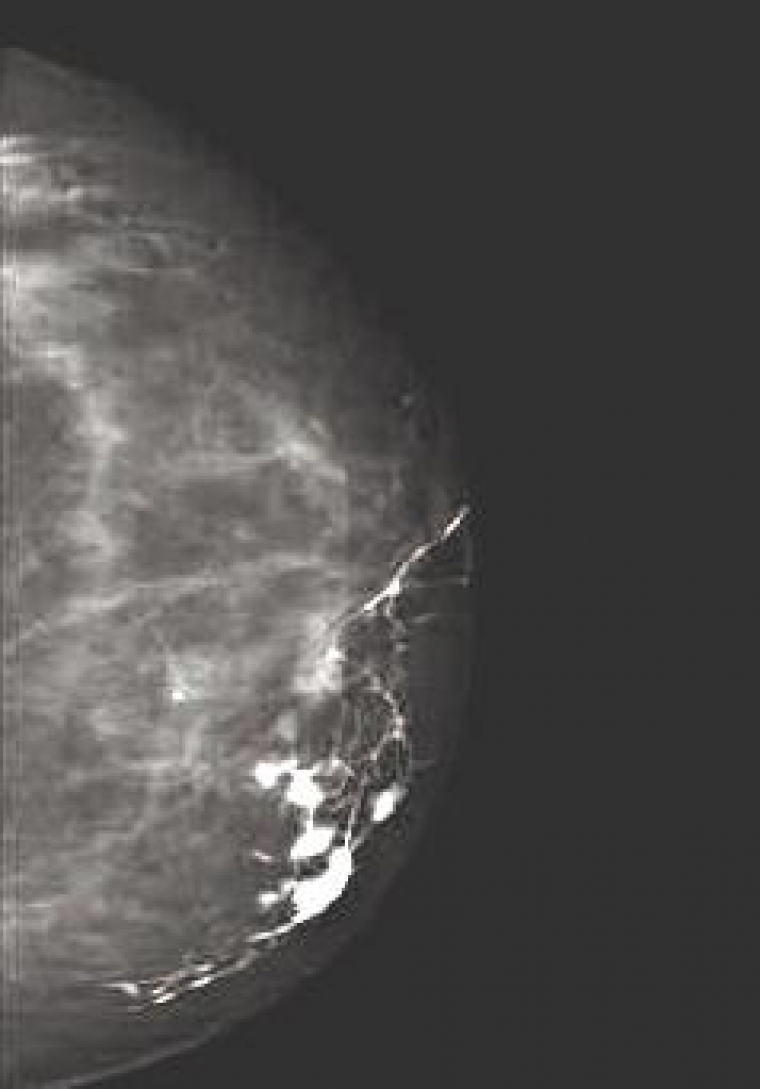

Particularité radiologique du sein

Le sein est un organe constitué de tissus mous. Il comporte des éléments hydriques (peau en surface, tissus glandulaires et conjonctifs en profondeur), des éléments graisseux (qui sont à l'origine du contraste radiologique) et des calcifications (dépôts calciques dans la fibrose, la nécrose, les parois vasculaires, la concentration de sécrétions glandulaires.) Les éléments hydriques et graisseux n’ont pas une grande différence d’atténuation, aussi les différences de contrastes sont faibles, or en mammographie, l’utilisation de produits de contraste reste limité à quelques cas très particuliers (exploration d’un canal galactophore par injection dans ce canal d’un produit à base d’iode, Figure 4). Pour obtenir un contraste suffisant, il est donc nécessaire que les rayons X ne soient pas trop perforants, c'est-à-dire utiliser un faible kilovoltage (typiquement entre 25 et 30 kV, contre souvent plus de 100 pour d’autres types de radiographie). L’information d’une mammographie est donc essentiellement contenue dans les nuances de gris (Figure 5), et il est essentiel que le film ne soit pas sur ou sous-exposé. Une bonne mammographie repose sur des choix judicieux (matériel, film, développement, etc…) et surtout sur l’expérience du radiologue. Une des difficultés de la lecture d’une mammographie provient du fait qu’un sein n’est pratiquement jamais dépourvu de diverses marques du passé (fibroses, kystes, opacités diverses) qui peuvent compliquer l’interprétation, quand ce n’est pas masquer un élément pathologique puisque les différents éléments se superposent sur le cliché. D’où, entre autre, l’intérêt de réaliser plusieurs clichés sous différents angles, et de comparer l’image radiologique des deux seins.

Les principales pathologies du sein et leur traduction radiologique

Le cancer est loin d’être la seule pathologie du sein, même si elle reste la plus grave. Dans la majorité des cas, heureusement, les anomalies détectées se révèlent être des tumeurs bénignes, des fibroses ou des kystes. Toutes ces anomalies, malignes ou bénignes, ont pour caractéristique d’apparaître comme des structures hydriques (présence de liquide ou amas fibreux), correspondant à des zones assez claires en radiographie au contraire des éléments graisseux qui apparaissent plus foncé.

Mammographie et cancer du sein

Le cancer du sein est le plus fréquent des cancers féminins, représentant 36 % de tous les cancers. Il est responsable de 19 % des décès féminins par cancer. Or la détection d’une tumeur de moins de un centimètre (indécelable à la palpation mais à la portée d’une mammographie) conduit le plus généralement à une guérison. C’est pourquoi les femmes de 50 à 74 ans (âge de plus grande survenue de la maladie) sont invitées à faire une mammographie (prise en charge intégralement) tous les 3 ans. Actuellement un peu plus de 40 % des femmes concernées suivent cette recommandation, ce qui reste insuffisant, même si ce taux augmente continuellement. En effet, on estime qu’une participation de 70 % des femmes à ce dépistage de masse augmenterait le taux de guérison de 30 %. En terme radiographique, un cancer est essentiellement détecté du fait de la présence de microcalcifications au niveau de la tumeur. Cependant, toute calcification n’est pas le signe d’une tumeur. En effet, on trouve des calcifications artérielles, des calcifications sous-cutanées, ainsi que des kystes de petite taille contenant du lait calcique. Il faut donc repérer les calcifications qui signalent la présence d’une tumeur. Pour cela, il existe une nomenclature qui permet l’évaluation du risque, essentiellement basée sur la taille, le nombre et la distribution des calcifications. Ainsi, les calcifications d’une taille supérieure au millimètre, de même qu’une microcalcification (inférieure au millimètre) isolée ne signalent pas un cancer. En fonction du nombre des calcifications, de leur aspect individuel, de l’aspect de l’amas, on peut donc évaluer la probabilité qu’il y ait une tumeur cancéreuse. A partir de ce moment, des examens complémentaires seront prescrits si nécessaire, en premier lieu desquels figure la biopsie qui permet l’analyste histologique des tissus suspects pour préciser le diagnostique.